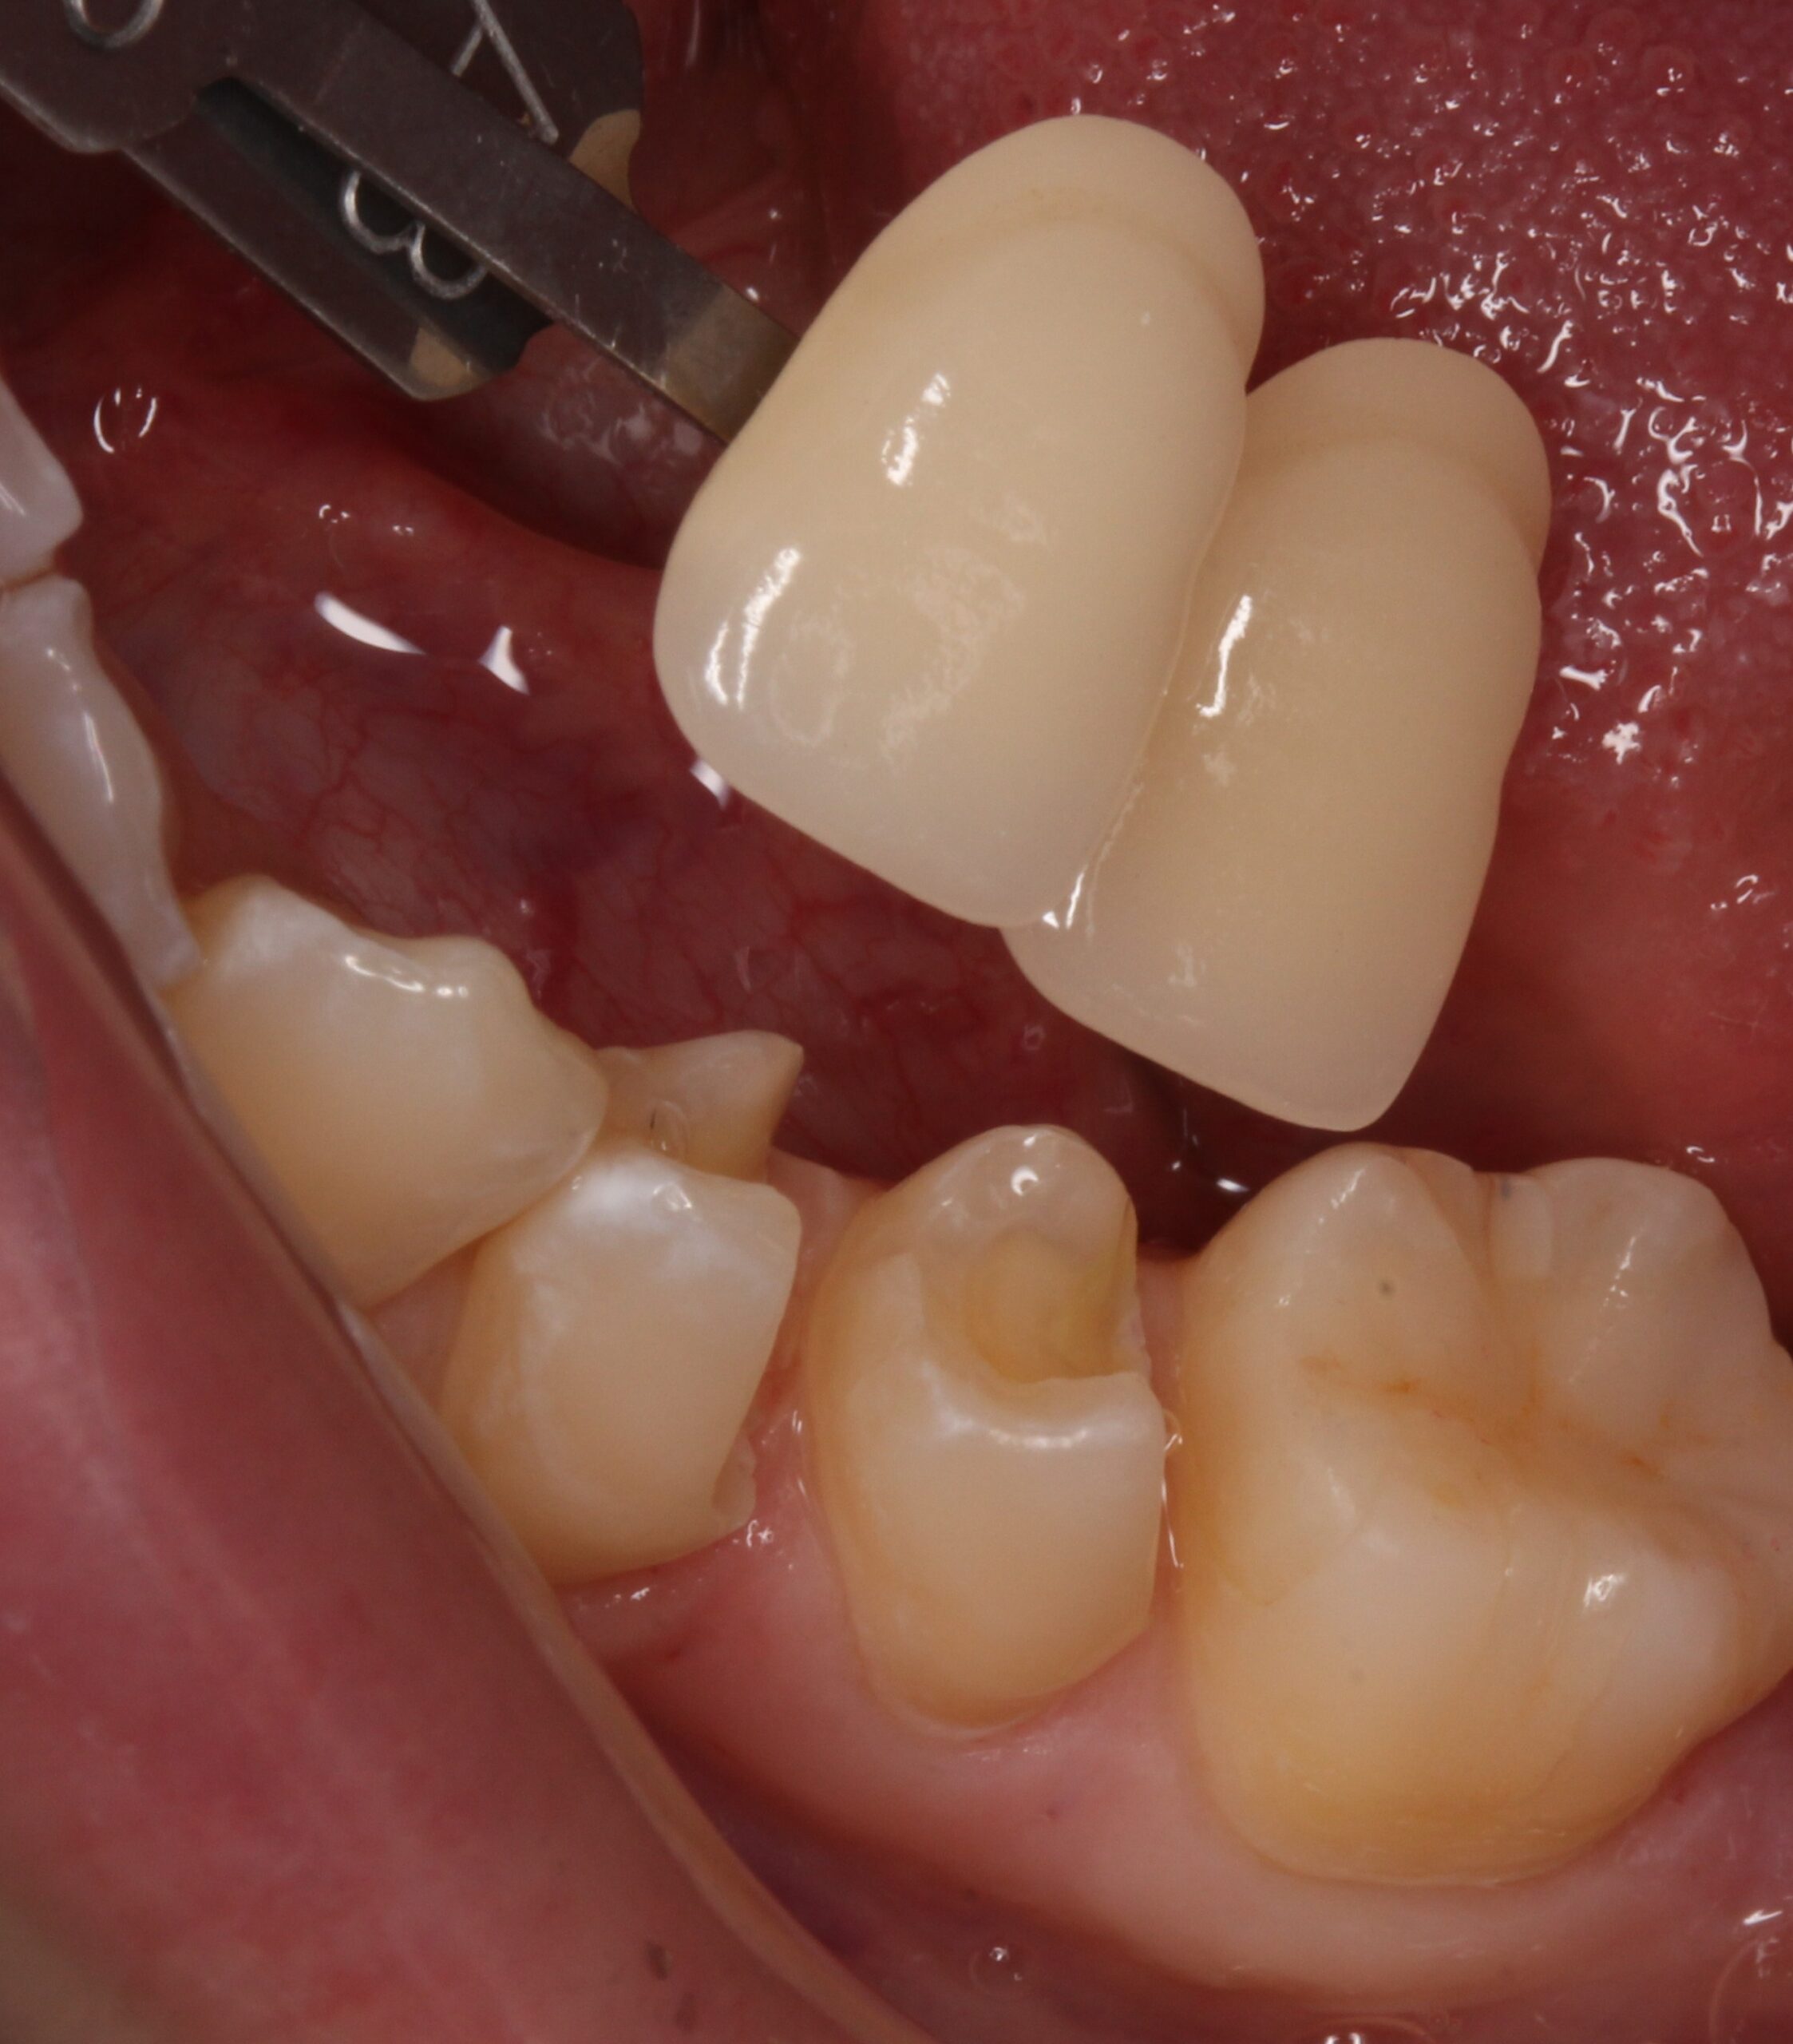

銀歯が取れた原因は?実は銀歯の中で虫歯が進行していました。

• Before

After